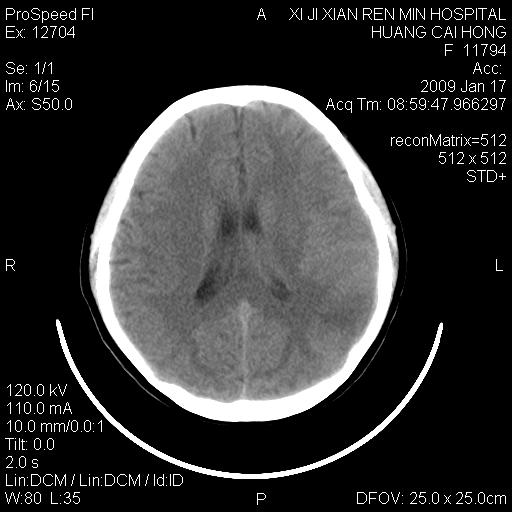

以下是引用zbp537在2009-1-19 13:54:00的发言:[br]首先考虑脑炎。[br]诊断依据:[br]1、患者较年轻。[br]2、有感冒病史。[br]3、左侧颞枕叶这么大一片低密度影,占位征象却不明显,不符合肿瘤特征,其内的高密度影为出血灶。

以下是引用xiaoniu在2009-1-19 13:29:00的发言:[br]左侧颞叶三角形低密度影,占位效应不明显,其内点片样高密都影,青少年患者,首先考虑:少突胶质瘤。因为有感冒病史,不能除外感染的可能。